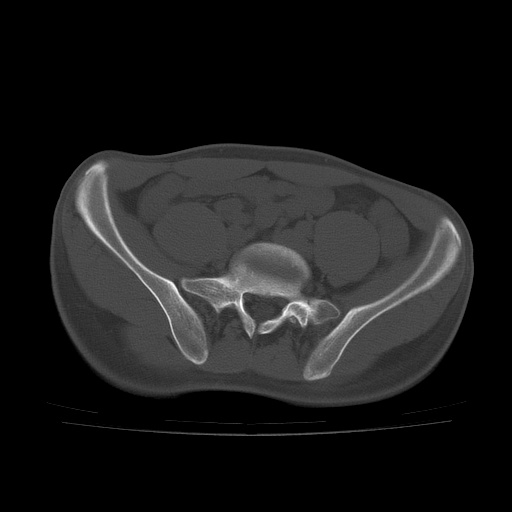

患者男性,18岁 腰腿痛1年  骶髂关节改变本人考虑强直性脊柱炎。

两侧骶髂关节骨质破坏,关节面毛糙,符合强直性脊柱炎骶髂关节改变。

符合强直性脊柱炎,虫蚀样骨质破坏。

两侧骶髂关节骨质破坏,关节面呈锯齿样改变关节间隙变窄,考虑强真性脊柱炎

双侧骶髂关节关节间隙变窄,边缘毛糙,关节面硬化,可见囊变!符合强直变现!

两侧骶髂关节骨质破坏以髂骨为主,间隙变窄,强直性脊柱炎